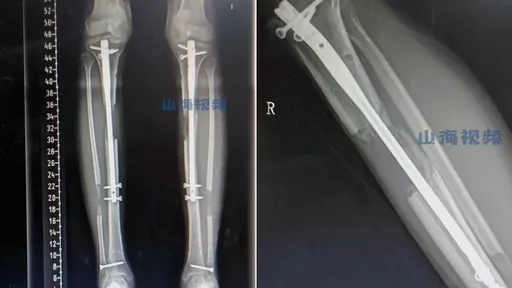

...女生,因為覺得自己太矮,於是到湖南省一家醫院做了「斷骨增高」手術,術後雖然如願長高了6公分,卻因為感...

...封,妹妹又在南韓讀書。因而自己已決定,要飛到南韓做斷骨手術。 而近來他也分享他最新情況,強調自己絕...